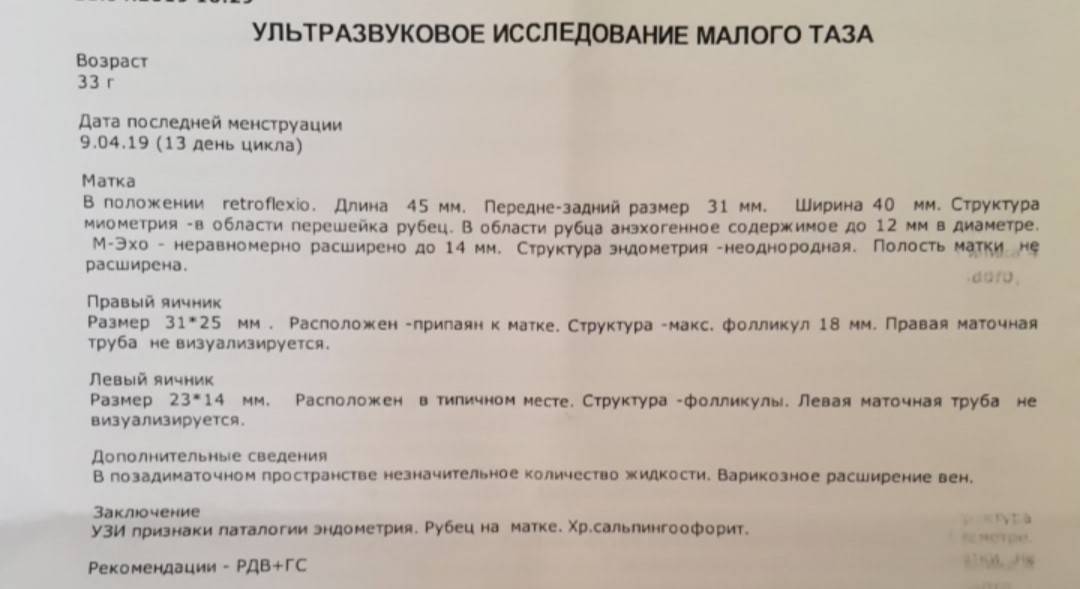

УЗИ малого таза

Почему разные заключения на УЗИ?